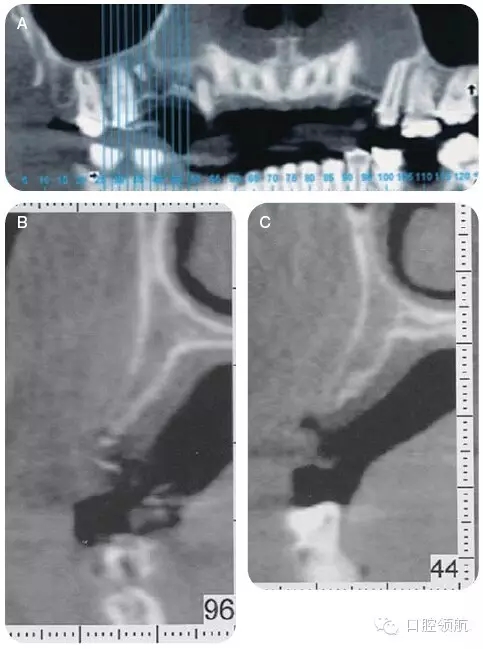

咨詢修復(fù)、牙體牙髓及正畸科,制訂詳細(xì)的治療計劃。行錐形束CT檢查上頜牙弓,以更好地了解缺損處牙槽嵴的形態(tài)及和上頜竇的鄰接關(guān)系(圖4)。

CT顯示牙槽嵴的垂直距離足夠,為更好地植入種植體,尚需有6~7mm的骨寬度。該區(qū)域的最終治療計劃包括:引導(dǎo)骨再生,修復(fù)以及咬合重建,包括#4-X-6種植體支持的局部固定義齒。

圖4 (A~C)CT檢查,顯示14號牙(左上頜第一磨牙)的牙槽嵴水平缺損。